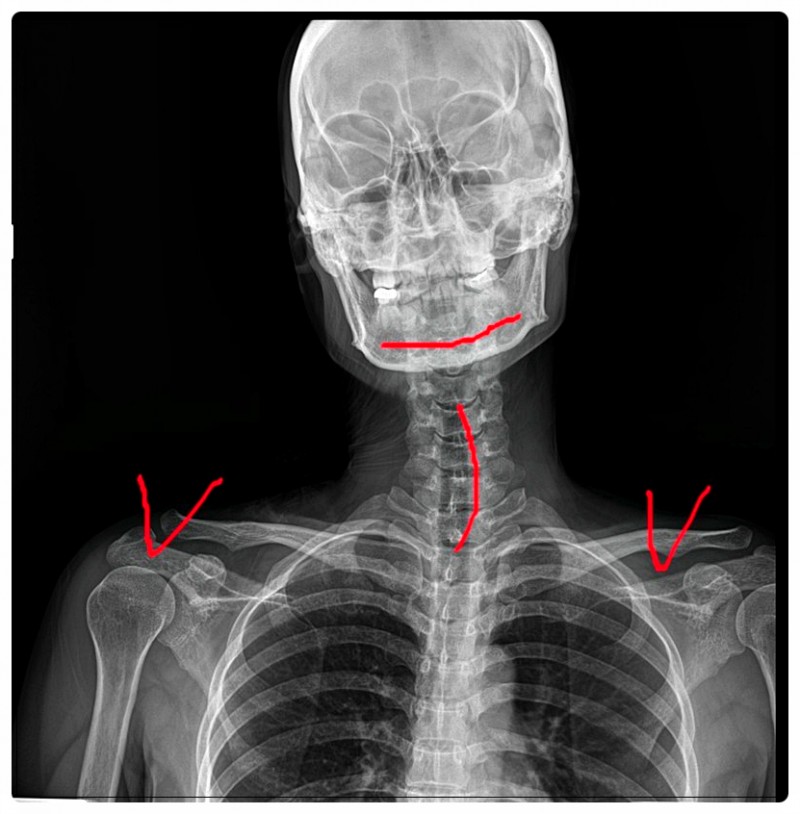

어깨통증, 목·척추·골반까지 확인해야 하는 이유

Q. 어깨가 아픈데 시작은 목일 수 있습니다.

어깨 근육 통증을 살펴볼 때

제가 가장 먼저 확인하는 곳이 바로 입니다.

어깨로 내려가는 대부분의 신경이 목, 특히 경추에서 시작되기 때문인데요.

경추의 정렬이 무너져 있거나 미세하게 불균형이 지속되는 분들이 있습니다.

이런 경우, 신경이 지나가는 공간이 좁아지면서

어깨 주변에 통증이나 저림이 나타날 수 있습니다.

Q. 그래서 저는 이렇게 접근하곤 합니다.

앞서 말씀드린 것처럼 저는 어깨통증을

하나의 부위 문제로만 보지 않습니다.

목–척추–골반의 정렬 상태를 함께 확인하며

통증의 원인이 되는 연결 구조를 단계적으로 살펴봅니다.

어깨 관절 상태뿐 아니라 자세 변화와 움직임 패턴까지 함께 확인합니다.